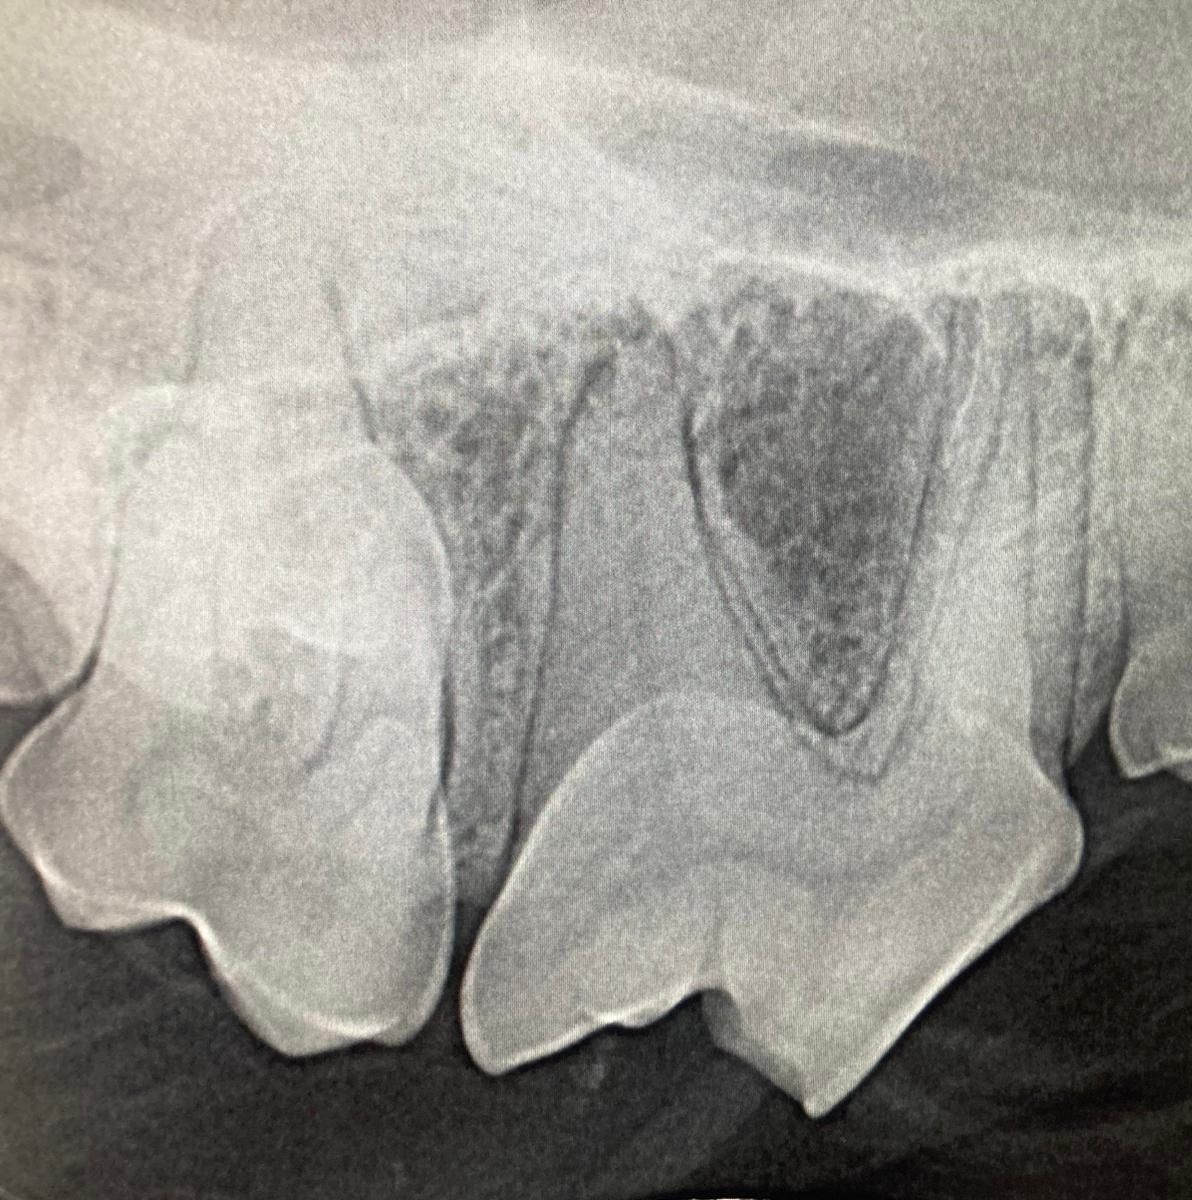

Digitale Röntgenologie